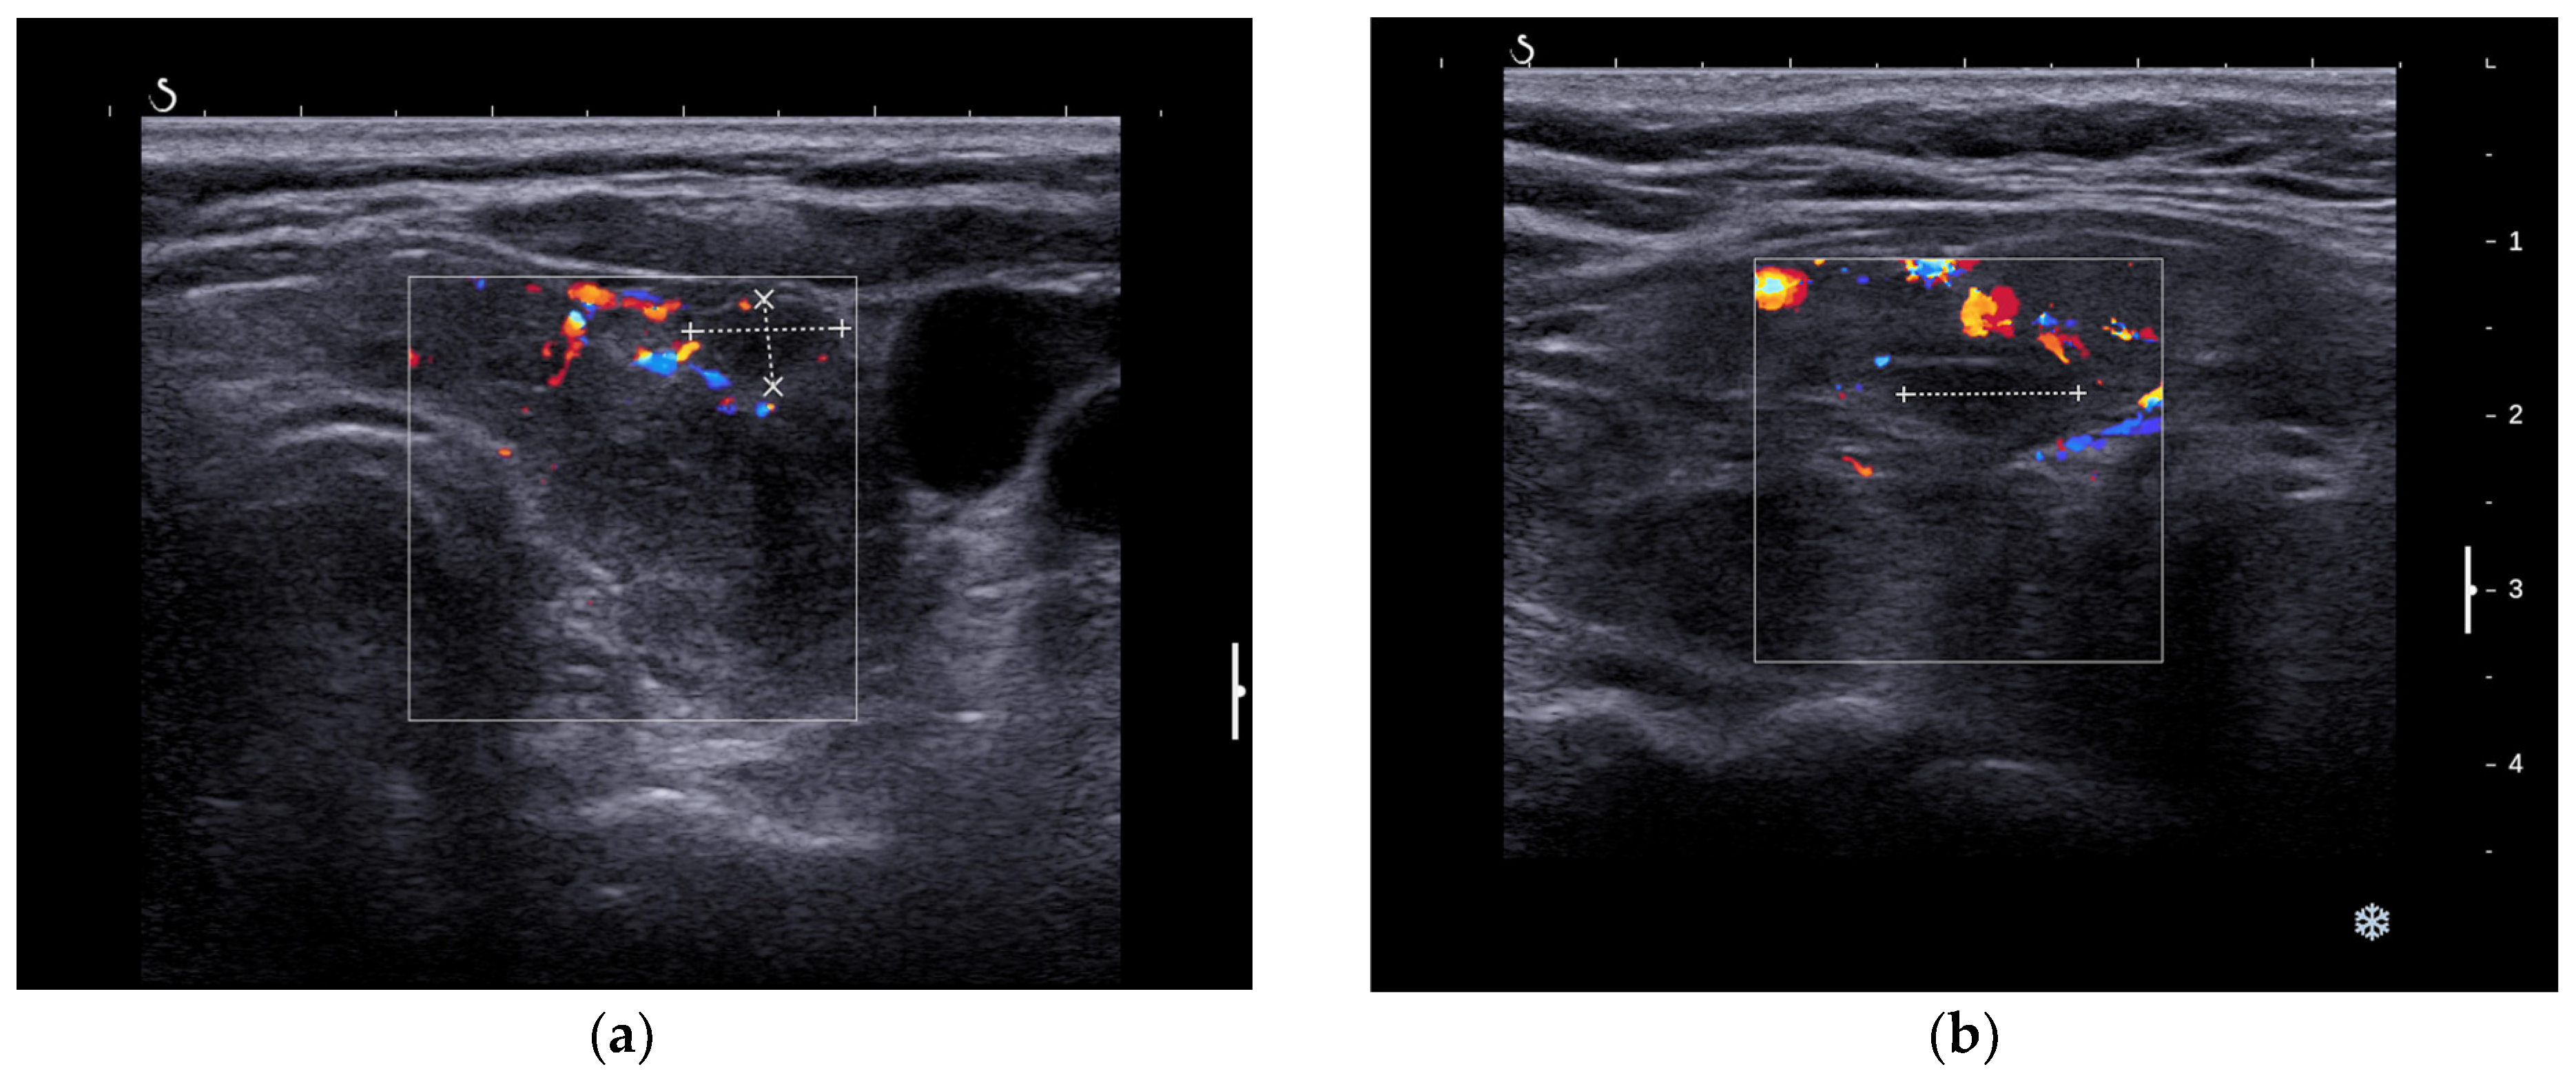

3.1.2. Thyroid Ultrasound

3.2.2. Thyroid Ultrasound

3.3.2. Thyroid Ultrasound